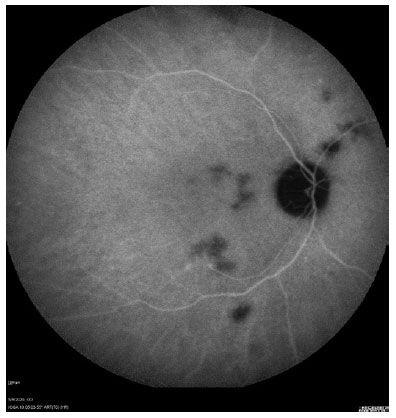

The results of the ophthalmic evaluation increased the possibility of disseminated sporotrichosis diagnosis. A skin biopsy was performed, and the culture was positive for Sporothrix schenckii. After the diagnosis of sporotrichosis, the patient reported a cat bite on his finger. Therefore, the patient was treated with intravenous amphotericin B, achieving full choroiditis recovery (Figure 2).

ICG is a cyanine dye that has ideal infrared frequencies to penetrate the retinal layers, allowing ICG angiography to image deeper circulation patterns than fluorescein angiography. Its importance is related to the detection of subclinical choroidal lesions and their follow-up(5). In this case report, ICG angiography revealed more lesions than was observed during fundus examination, and it was useful to assess choroiditis recovery. In conclusion, ICG the exam showed a different pattern of choroiditis related to sporotrichosis from those previously described.